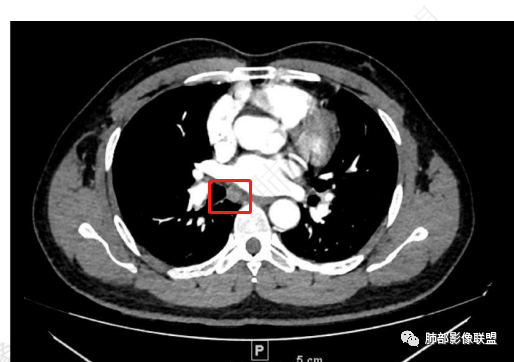

2、胸部CT右肺下叶胸膜下肿块性病变,边缘可见分叶毛刺、边缘膨隆,似有指状凸起,邻近胸膜稍牵拉凹陷,叶间裂以为不明显,提示收缩力较弱。近端支气管进入后截断,病灶内密度尚均匀,增强后可见轻度强化,未见空洞或钙化,并可见血管影进入。右侧肺门及纵隔内可见肿大淋巴结影。无胸腔积液。

3、综合患者临床症状及影像表现,需要考虑肿瘤性病变和非肿瘤性病变,肿瘤性病变需要考虑普通浸润性腺癌或结节型粘液腺癌、淋巴瘤、淋巴上皮瘤样癌、小细胞肺癌等,非肿瘤性病变主要考虑肺脑同病中的隐球菌。①普通浸润性腺癌,以肺外周多年、混合磨玻璃或实性结节/肿块,多见分叶、毛刺、胸膜凹陷、血管集束等征象,本例收缩力较弱、且强化偏轻,不够典型。②粘液腺癌,腺癌的特殊类型。多位于胸膜下(90%位于胸膜下,70%位于下叶胸膜下),边缘清或不清的GGO:提示粘液外渗,少数为纯GGO,缺乏中心纤维化区:毛刺、胸膜凹陷征少,很少胸膜侵犯,淋巴结转移少见,增强后无强化或低强化,本例病灶位于胸膜下,强化轻,收缩力弱,结节期粘液腺癌确实可以符合。③小细胞肺癌,吸烟男性多见,典型征象包括娘小崽大、腊肠样凸起、冰冻纵膈等,本例胸膜下病变大、但肺门淋巴结肿大程度较轻,不符合常见小细胞癌生物学行为,但有可疑指状凸起,小细胞肺癌不能完全除外。④淋巴上皮瘤样癌,少见的恶性肿瘤,患病年龄较轻,肿瘤多位于胸膜下,边缘多光滑,病灶周围可见磨玻璃,毛刺及分叶、胸膜凹陷少见,近端支气管可截断,增强多为中度-明显强化,本例除了强化程度偏轻外,影像表现基本可符合。⑤淋巴瘤,原发肺内淋巴瘤较少见,病灶多位于支气管血管束周围或胸膜下,密度多较均匀,边缘可膨隆也可平直收缩,可见支气管充气征、血管造影征等,强化多为轻中度,本例肺内结节血管穿行自然,局部有血管漂浮,长轴与支气管走行基本一致,肺门淋巴结肿大,不能排除。⑥隐球菌,影像表现可分为孤立结节型、大片实变型、多发结节或实变型、弥漫型。病变多位于胸膜下,边缘平直为主、可伴晕征,可见支气管穿行、部分可见支气管截断,密度多较均匀,部分可伴空洞,增强多为轻中度强化、延迟强化。本例病变位于胸膜下,收缩力弱,强化程度轻,但没有呼吸道症状,病变近端支气管截断,肺门淋巴结大,这些征象都难以用隐球菌解释,基本排除。